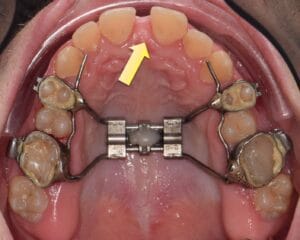

1-The smile, because upper jaw narrowness will lead to “Black corridors” on the corner of the mouth during smiling, as we see in the following case, and we will notice a great improvement on the smile and the incredible increase of the white color of the teeth, during smiling after we did expansion of upper jaw transversely.

Expanding upper jaw may lead to the appearance of a gap between upper central anterior teeth. The appearance of this gap is something good and indicate to a successful upper jaw expansion, this space may remain temporarily for some time and gradually it will be closed either spontaneously or through orthodontic braces.